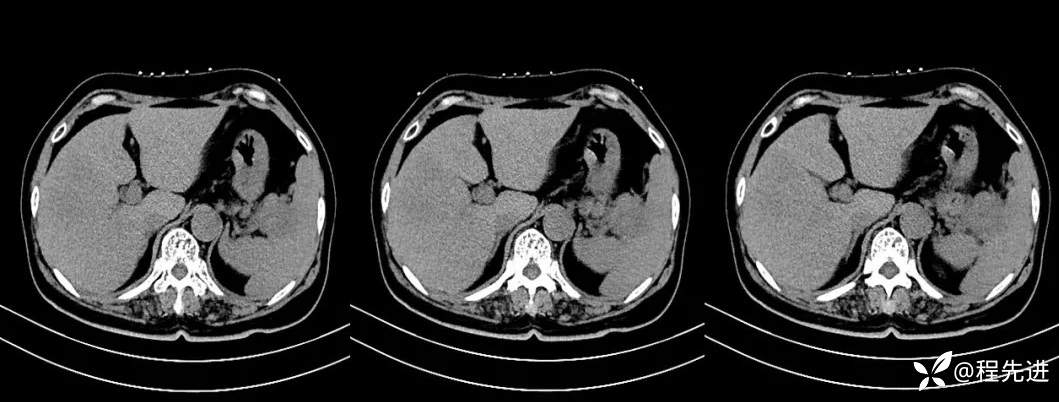

【现病史及既往史】:体检发现胰尾部肿块4年,当时手术病理提示异常增生性病变,现发现右侧顶部包块,逐渐增大,无明显感觉不适

影像检查: